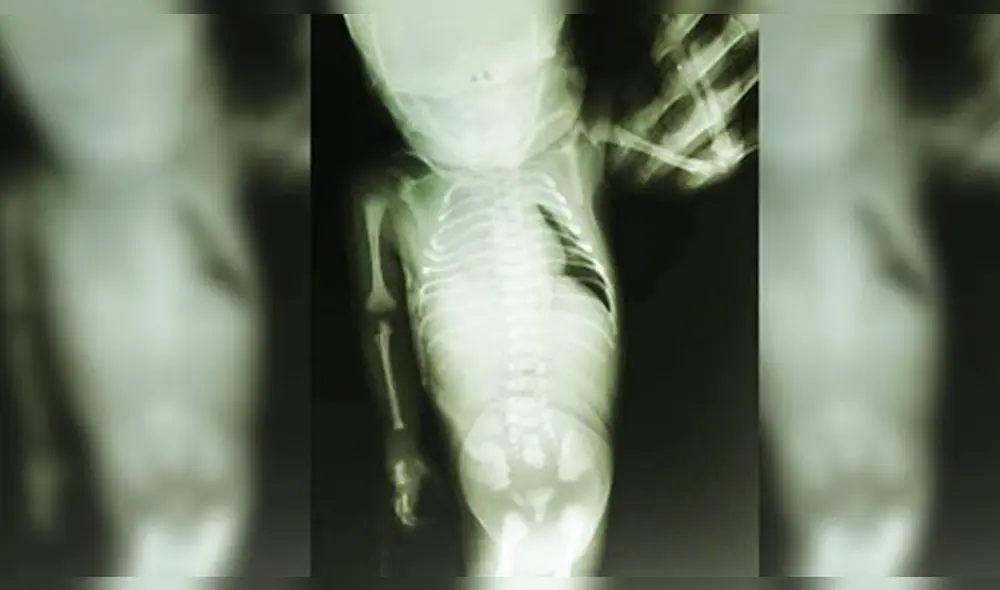

Cajamarca: muere ''niña sirena'' nacida en hospital de Jaén

Además de la malformación congénita denominada Sirenomelia, la bebé nació con otras complicaciones relacionadas con el funcionamiento del riñón y la vejiga.

Según se conoció, era la primera bebé de una pareja joven; la niña llegó con una malformación congénita que recibe el nombre de Sirenomelia, además de otras complicaciones relacionadas con el funcionamiento del riñón y la vejiga.